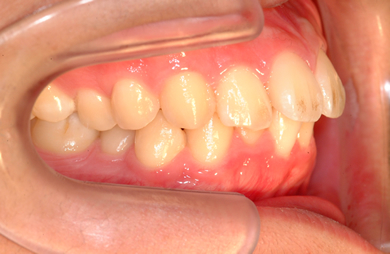

| 性別/年齢 | 男性 / 24歳 | ||||||||||||||||||||||||||||||||

| 主訴 | 乱ぐい歯を治したい。 | ||||||||||||||||||||||||||||||||

| 治療方針 | 歯のがたつきが大きいことより上下左右第一小臼歯を抜歯して、マルチブラケット装置にて治療。また、親不知がまっすぐ生えることができず横を向いている状態なので、まっすぐにする隙間があることから親不知も使用し、矯正を行う。 | ||||||||||||||||||||||||||||||||

| 治療内容 | 唇側矯正(ホワイト) | ||||||||||||||||||||||||||||||||